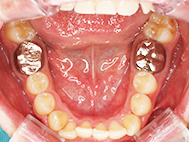

Before

| 症状 | 上顎前歯部叢生 |

上の前歯がハの字隣の歯が引っ込んでいる

前歯のガタガタが気になるとの事で来院されました。

装着が目立ちたくないとの事でアライナ-での矯正を希望されました、歯の間を削り少し歯の幅をスリムにして綺麗なアーチに並びました。